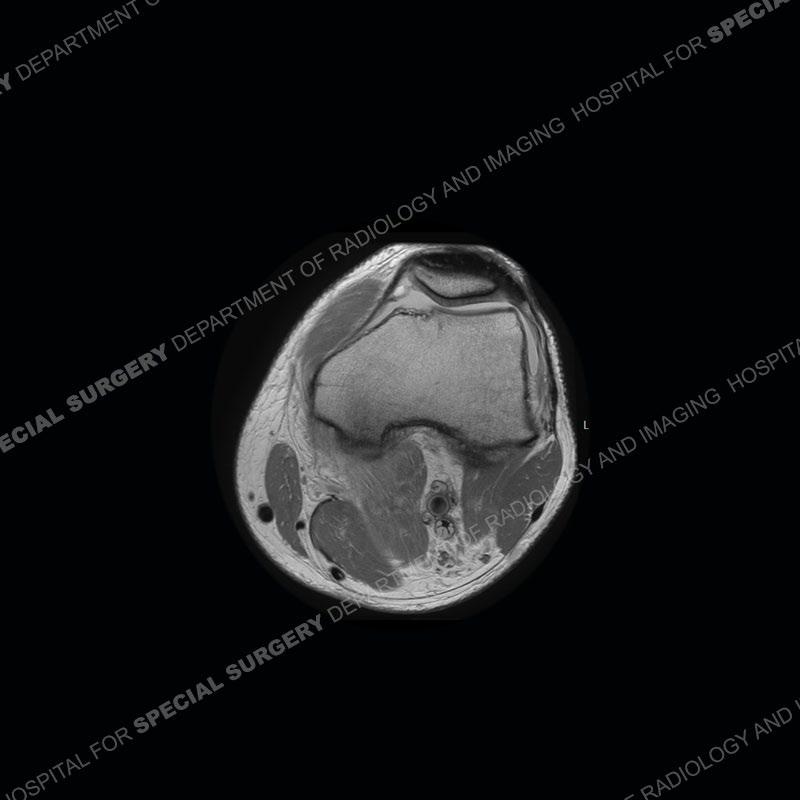

The radiographs show degenerative change of the medial compartment and a varus knee, but they are not germane to this case. No acute bony injury is present. The MRI shows edema of the posterior medial knee/soft tissue and a focal area of a partially disrupted low signal structure. The details are kept at a minimum in the findings of this case on purpose.

Diagnosis: Partial Disruption Medial Head Gastrocnemius (MHG)

Fourth, use all imaging planes and different pulse sequences to make your diagnosis. The edema highlighted in this case can be seen as the obscuration of fat on the PD images but is much easier to perceive as the high signal on the IR pulse sequences. The actual disruption of the MHG myotendinous junction is only able to be seen on the axial images. On the sagittal and coronal images, we get a sense something is wrong but hard to be exact. Lastly, when you look at a study and something just seems off (as I would say the sagittal and coronal images do with that dark band of tissue posteriorly), listen to yourself and go through the study slowly and meticulously. Most of the time you will find you were right, and something indeed is present.